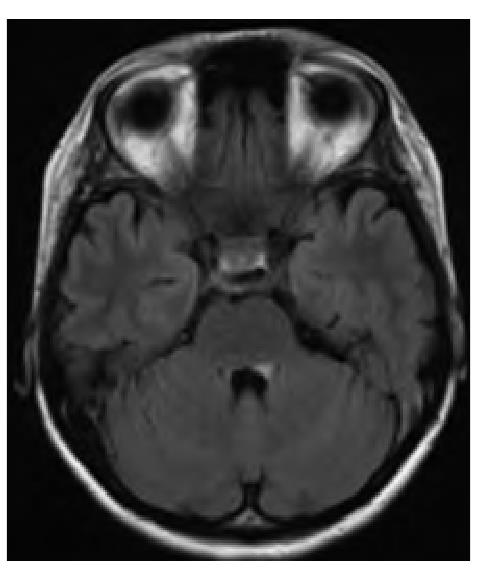

Спустя ещё 7 дней пациентка отметила появление лёгкой диплопии и усугубление головокружения. В неврологическом статусе выявлялась мозаичная гипестезия левой половины лица без разницы по зонам Зельдера и ветвям тройничного нерва, снижение конвергенции левого глаза. В остальном в неврологическом статусе отклонений не было. Спонтанный нистагм, косоглазие, мозжечковая и бульбарная симптоматика не выявлялись. Учитывая клинические признаки поражения ствола мозга, была проведена повторная МРТ головного мозга, по результатам которой в режиме T2-FLAIR выявлен гиперинтенсивный очаг в области дна IV желудочка, соответствующий локализации area postrema (рис. 1).

Рис. 1. МРТ пациентки в режиме FLAIR.

Визуализируется мелкий очаг слева, прилежащий ко дну IV желудочка.

Fig. 1. Patient's FLAIR MRI image.

A small left-side lesion is visualized adjacently to the floor of the IV ventricle.